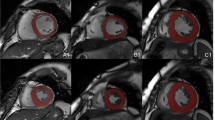

This study investigated the discriminability of quantitative radiomics features extracted from cardiac magnetic resonance (CMR) images for hypertrophic cardiomyopathy (HCM), dilated cardiomyopathy (DCM), and healthy (NOR) patients.

The data of two hundred and eighty-three patients with HCM (n = 48) or DCM (n = 52) and NOR (n = 123) were extracted from two publicly available datasets. Ten feature selection methods were first performed on twenty-one different sets of radiomics features extracted from the left ventricle, right ventricle, and myocardium segmented from CMR images in the end-diastolic frame, end-systolic frame, and a combination of both; then, nine classical machine learning methods were trained with the selected radiomics features to distinguish HCM, DCM, and NOR. Ninety classification models were constructed based on combinations of the ten feature selection methods and nine classifiers. The classification models were evaluated, and the optimal model was selected. The diagnostic performance of the selected model was also compared to that of state-of-the-art methods.